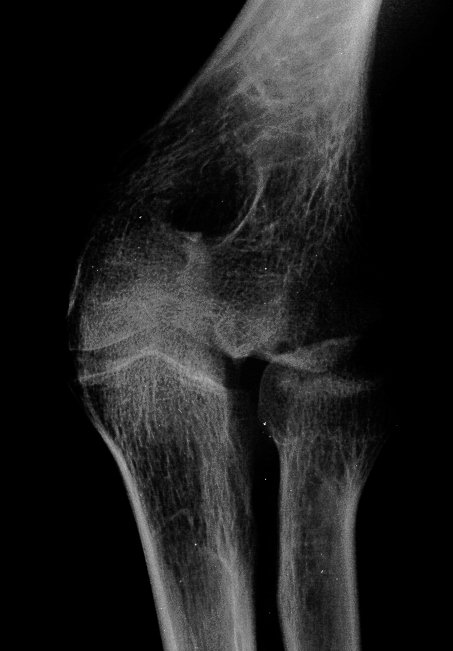

Initial injury: supracondylar fracture in a 9 year old:

Five years later, he has limited motion (E/F 35/100) and painful clicking with elbow flexion and extension.

Plain films show humeral osteophytes and posttraumatic changes of the capitellum and radial head.